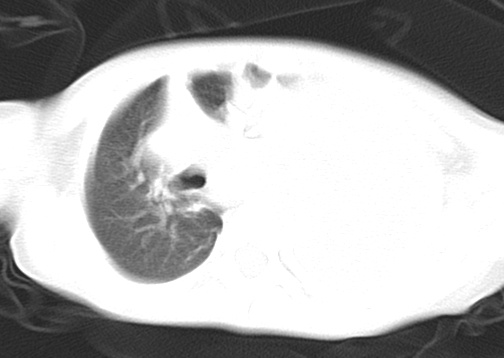

患儿 女 4岁,发热 咳嗽 胸透 考虑:左侧脓胸

左侧胸廓内见大量密实阴影,肺尖部尚有少量肺组织影,纵膈明显受压移位,肋骨未见明显受侵征象,虽然病人年龄较小,但如此大量的“积液”,还是要警惕,不同意一般感染,可结合穿刺脱落细胞学检查。

1)考虑左肺炎症感染。2)左侧大量胸腔积液。

1)考虑左肺炎症感染。2)未经穿刺只能定左侧大量胸腔积液。

左侧张力性大量胸腔积液压迫性肺不张、感染;建议治疗后复查。